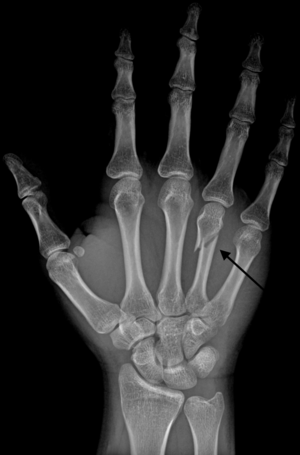

Diagnosis by a doctor’s examination is the most common, often confirmed by x-rays. X-ray is used to display the fracture and the angulations of the fracture. A CT scan may be done in very rare cases to provide a more detailed picture.